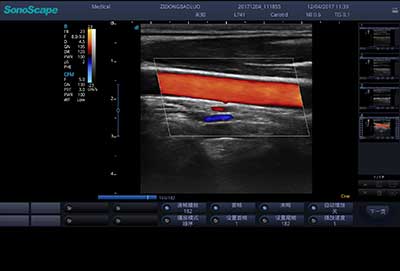

E3便携式彩色多普勒超声诊断系统拥有专业超声技术平台、高度集成化的硬件模块和结构设计、简便的操作流程、支持三探头接口全激活,兼顾了优质图像、轻便机身以及台便两用的临床使用需求。无论在常规超声科门诊检查,还是在急诊、麻醉、ICU、户外等各种应用场景。都能给您带来流程的操作体验。

一键自动优化